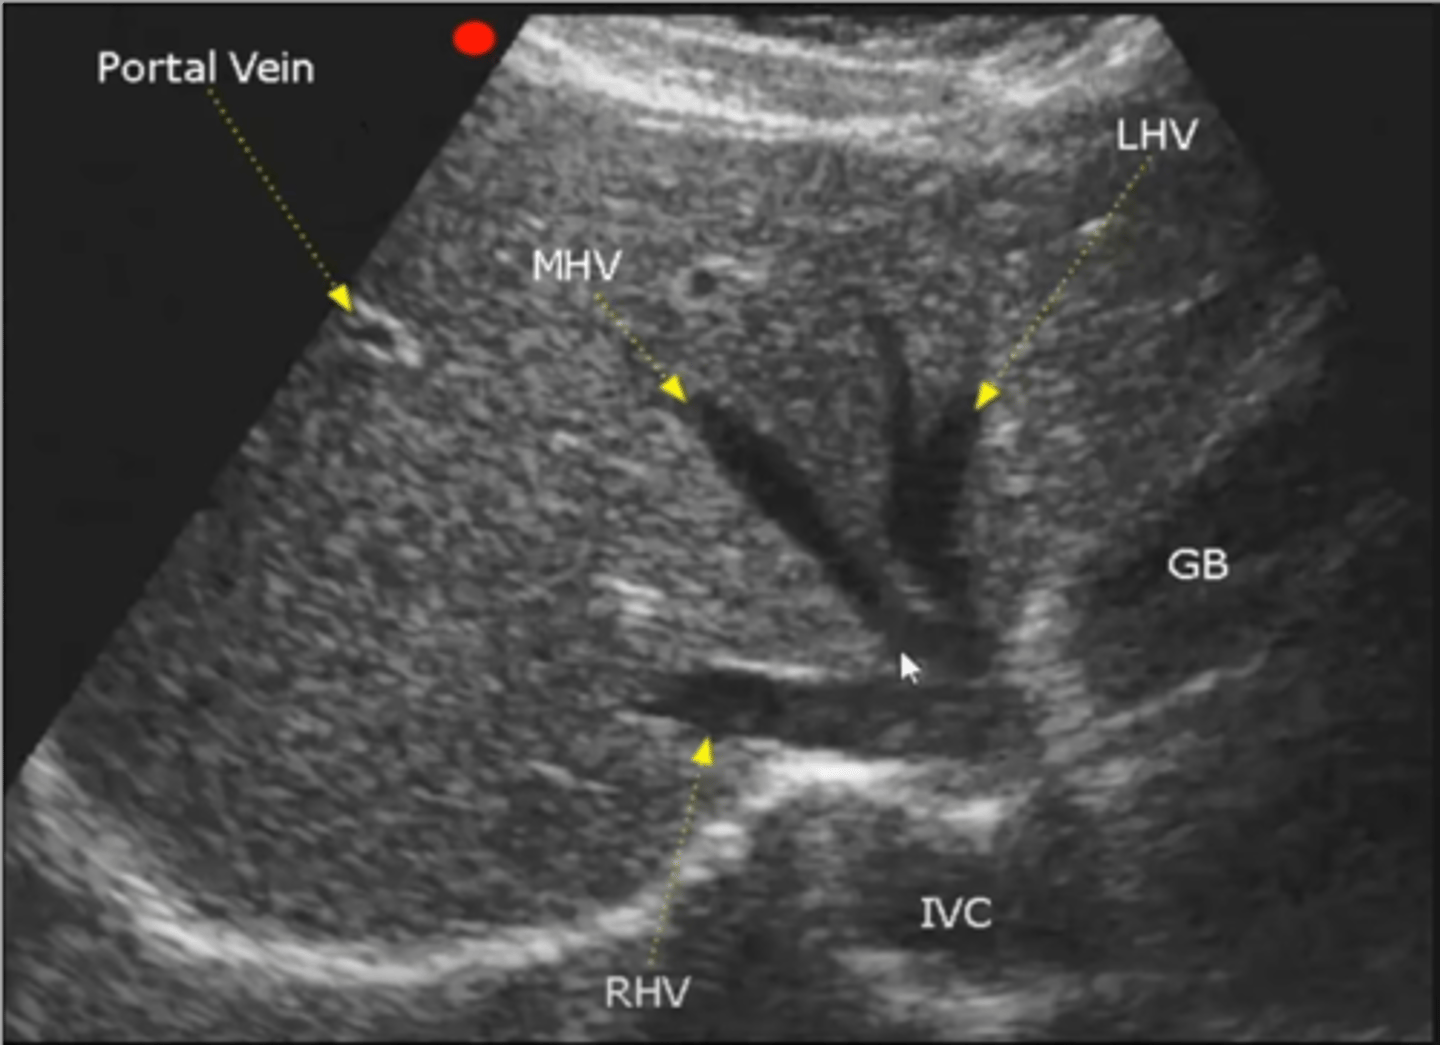

Right lobe of liver and hepatic veins on US